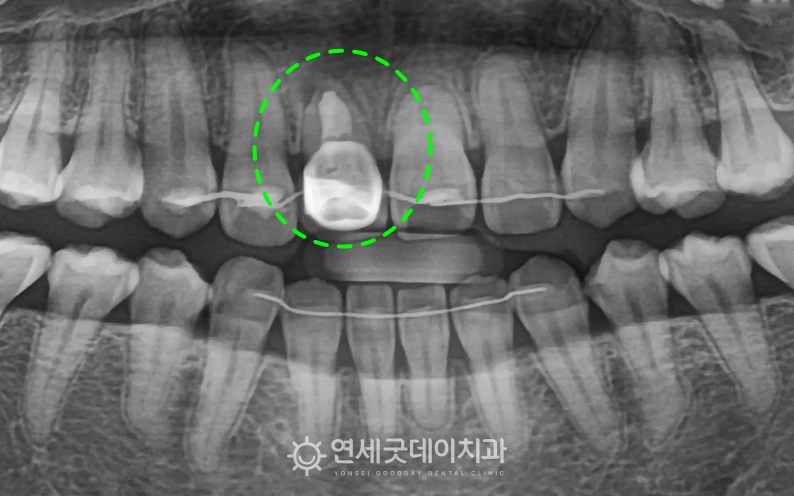

환자분은 타원에서 오른쪽 앞니 잇몸에 구멍이 나서 확인해보니 앞니 입술쪽(buccal)의 뼈가 얇고 또한 뿌리 주변을 감싸는 뼈 높이가

앞니는 구조적으로도 잇몸뼈가 얇은 편인데, 환자분은 앞니 발치 후 i-GBR을 통해 잇몸뼈 두께를 보강하고

발치한 치아의 뿌리 끝이 손상되었으며

발치 부위는 두툼한 잇몸뼈 재생을 위해